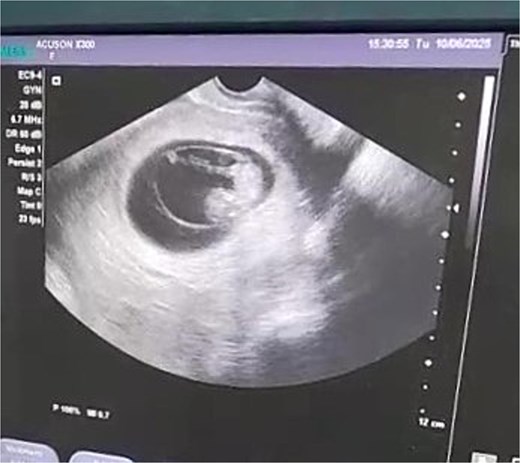

On admission, she appeared pale with mild abdominal tenderness. Vital signs: BP 90/60 mmHg, pulse 91 bpm, temperature 37°C, SpO₂ 95%. Transvaginal ultrasound demonstrated a 10-week intrauterine pregnancy with positive cardiac activity (Fig. 1); adnexa were not assessed. Initial labs showed anemia (Hb 9.1 g/dL) and leukocytosis (WBC 13000/μL).

Transvaginal ultrasound showing a 10-week intrauterine pregnancy with positive cardiac activity.